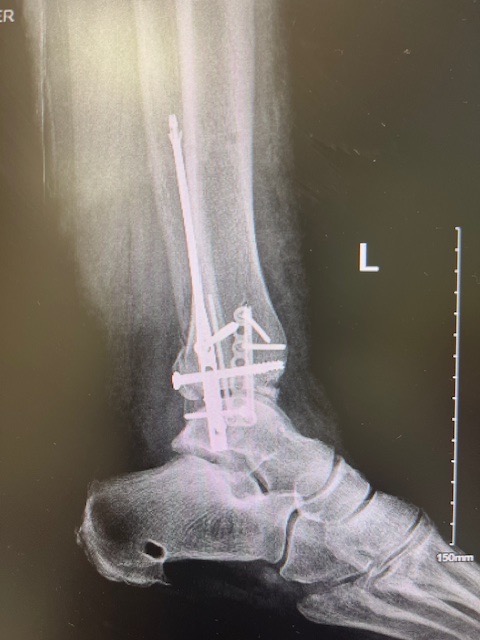

While in the hospital, I have had two surgeries on my ankle. The first one was to stabilize the bones, which involved screwing six 12-inch rods into my ankle, foot, and shin. My surgeon took it upon himself to wrap my foot and leg so I couldn’t see what was going on there, but seeing these metal rods sticking out and feeling the pain was bad enough.

A few days later, I had THE surgery where they took out the rods and placed metal plates and screws in my ankle and foot. …And here I am, 09/24, still in the hospital. My mobility is terrible. I am on my way to a rehabilitation facility in the Bronx.